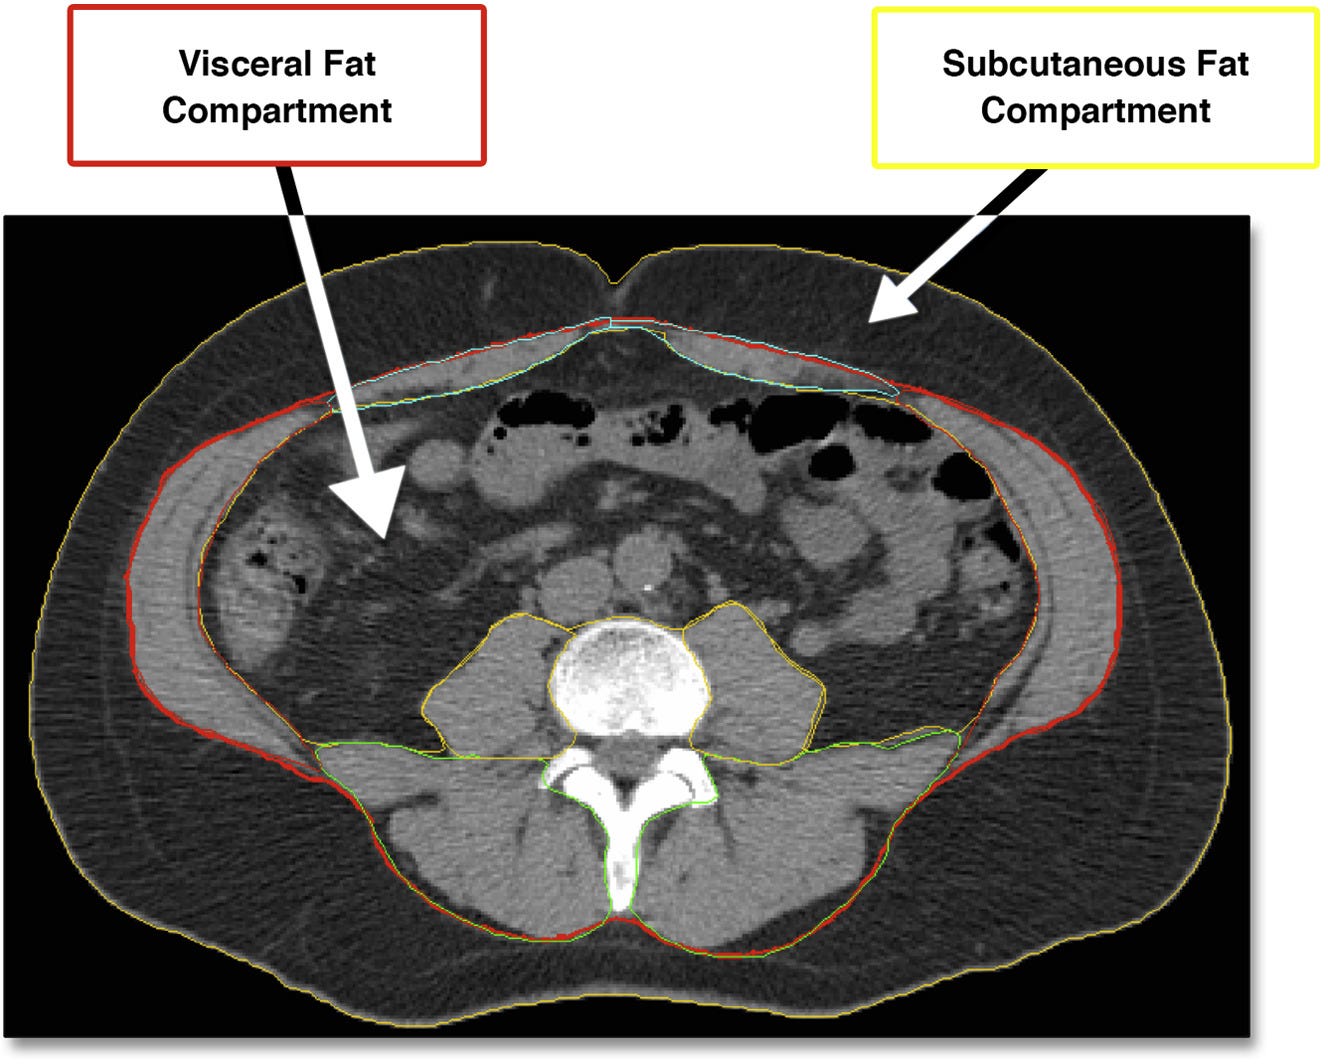

And these brain changes are in turn linked to increased body fat – in particular visceral adiposity, the accumulation of fat within the abdominal cavity. While subcutaneous fat accumulates just under the skin, far from any metabolically important organs, visceral fat is stored around vital internal organs including the liver and pancreas:

Visceral fat releases biochemicals which set off a chain of inflammation throughout the body, including the brain. The neuroinflammatory damage initiated by excess deep belly fat is believed to cause the brain pathologies described above, that result in diminished fluid intelligence.